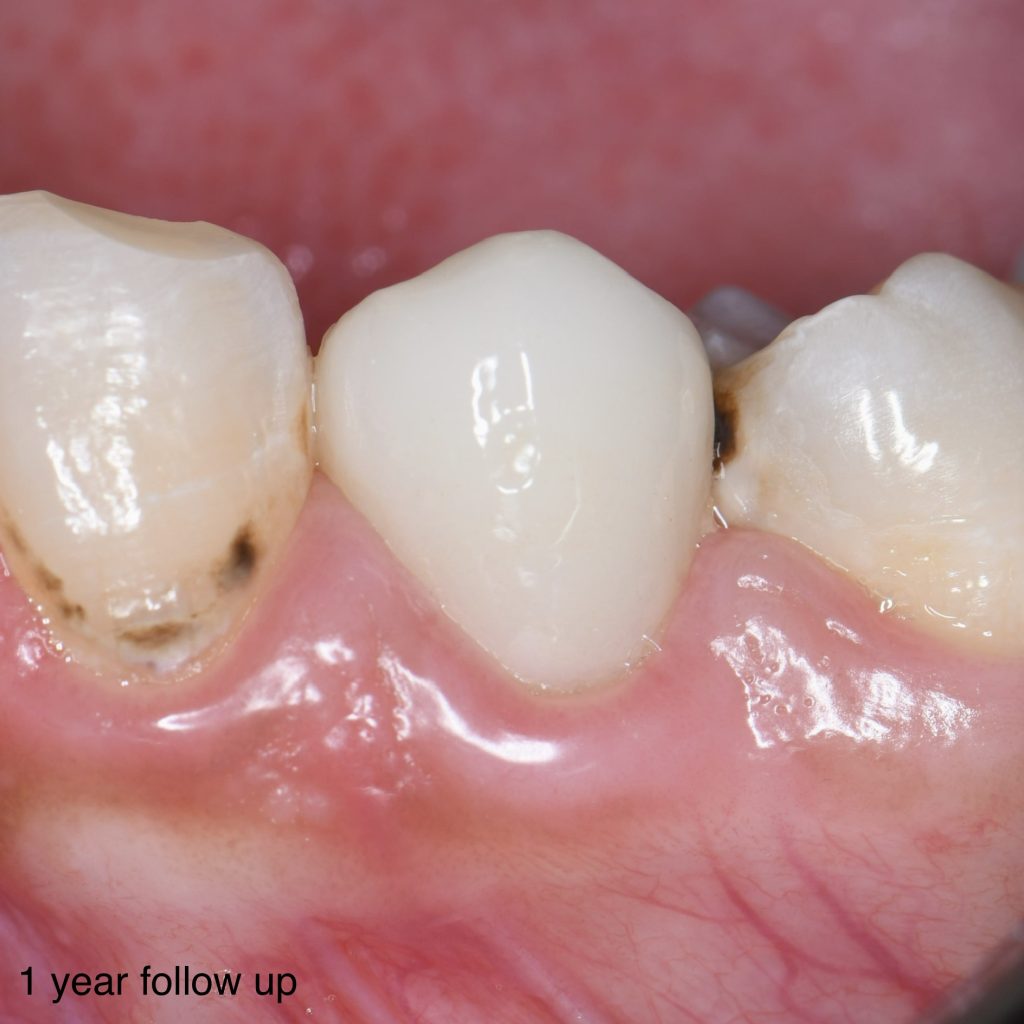

Follow up the case for more 1 year and still with good condition, aesthetic, functional and healthy

1 year follow up